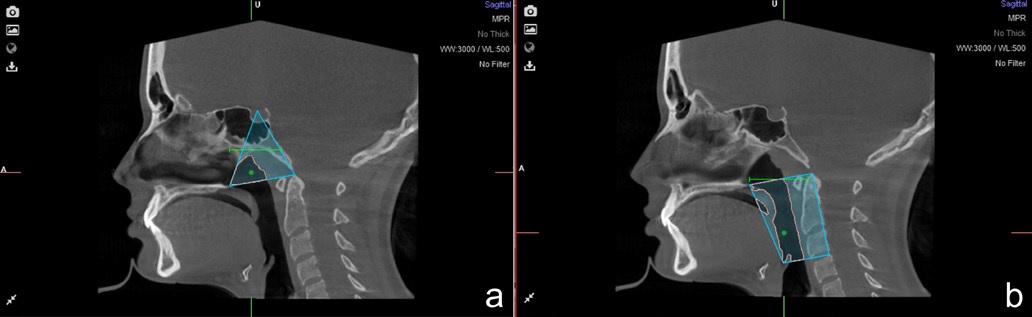

The limits of the nasopharynx and the oropharynx were determined for the upper airway assessment. The following landmarks were identified as the nasopharynx boundaries: (1) posterior nasal spine, (2) sella, and (3) the odontoid process tip, forming a triangle (Figure 2a). For the oropharynx, four anatomic points were identified: (1) posterior nasal spine, (2) epiglottis tip, (3) odontoid process tip, and (4) posterior superior border of the fourth cervical vertebra (Figure 2b). Afterward, the software calculated the corresponding volume in cubic centimeters (cm3) and the minimal sectional area in square millimeters (mm2). The sum of both nasopharynx and oropharynx volumes represented the total upper airway volume.